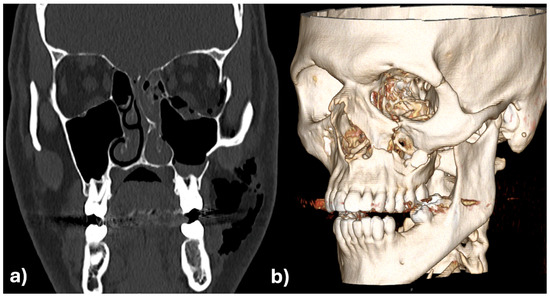

The initial assessment showed facial asymmetry, periorbital swelling, and diplopia. Clinical examination revealed depression of the zygomatic arch on the left side and restricted ocular movement. CT scan confirmed fractures of the zygomatic-maxillary-orbital-complex, with significant displacement of the zygomatic bone and herniation of orbital contents into the maxillary sinus (Figure 7a,b).

Figure 10a,b are showing the images of the intraoperative 3D C-arm scan and Figure 11 shows the image fusion between plan and achieved result.

Figure 7. Zygomatic-maxillary-orbital-complex fracture of the left side in coronary view (a) and as 3D reconstruction (b).

Figure 10. 3D (a) and in coronal view (b) of the intraoperative 3D scan which shows an almost perfect anatomic reconstruction and fit of the patient specific implants.